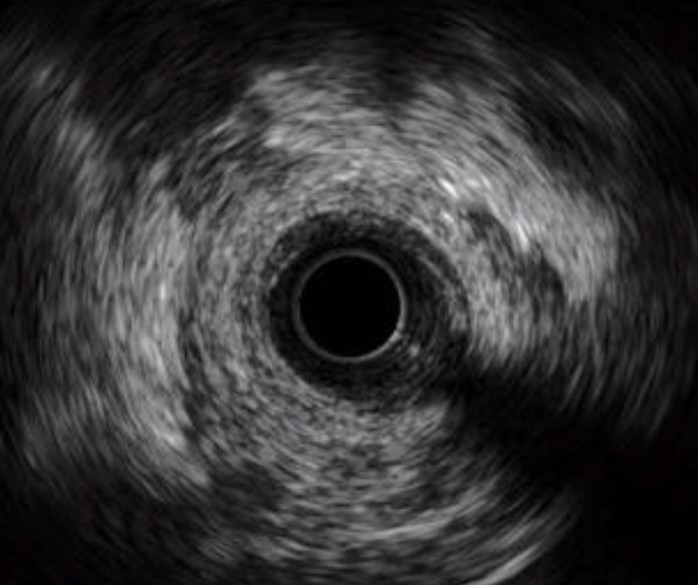

OPTICROSS HD Imaging Catheter vs. Competitor

High-Definition IVUS image quality helps physicians more accurately identify lesion length, assess plaque morphology, and determine the tools required for vessel prep. See how OPTICROSS HD’s 60 MHz images stack up against the competition.

Philips Volcano Eagle Eye Platinum Imaging Catheter 20MHz

IVUS image of inside a coronary vessel using the 20MHz Philips Volcano Eagle Eye Platinum catheter

Axial resolution: <170 µm

Philips Volcano Revolution Imaging Catheter 45MHz

IVUS image of inside a coronary vessel using the 45MHz Philips Volcano Revolution Platinum catheter

Axial resolution: 50 µm

OPTICROSS versus OPTICROSS HD images courtesy of Michael Kim, MD, FACC, FSCAI North Colorado Medical Center